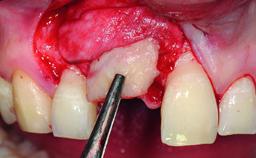

Replacement of a Missing Upper Left Central Incisor: Late Placement of an RC Bone Level Implant, CAD/CAM Zirconia Abutment

A healthy 37-year-old female patient was referred for a consultation on the replacement of missing tooth 21 with an implant-supported restoration. She stated that several years previously the tooth had been traumatically avulsed following a motor vehicle accident. The tooth was replaced with a three-unit fixed partial denture (FPD) immediately afterwards. Over time, she became disillusioned with the FPD and looked for a different option, including orthodontic therapy. She presented still in her orthodontic appliances, with the pontic sectioned free from the FPD but attached to the archwire. Her orthodontist felt that orthodontic treatment had been successfully completed, but nevertheless referred her before removing the appliances in case adjustments were necessary.